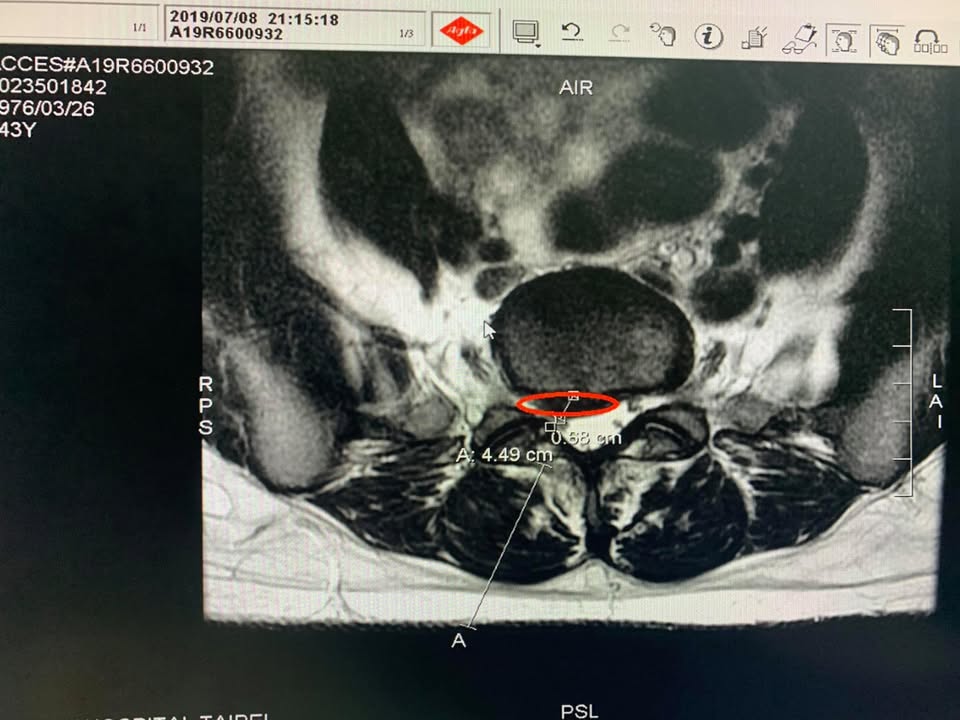

💢康小姐抱怨從今年三月底開始右側屁股跟大腿後側開始痛,四月底就很痛,去傳統復健科診所拉了三個月的腰效果不如預期,走路比較久就開始痛,痛連大腿後側,每天下午大約四五點就開始痛,今年七月十五號去國泰醫院拍攝MRI,證實腰椎L5S1椎間盤脫垂壓迫硬膜與右側神經根,神外醫師建議開刀,患者畏懼開刀,所以來嘗試脊椎整合中醫微創療法

診斷: 腰椎L5S1椎間盤脫垂壓迫硬膜與

右側神經根